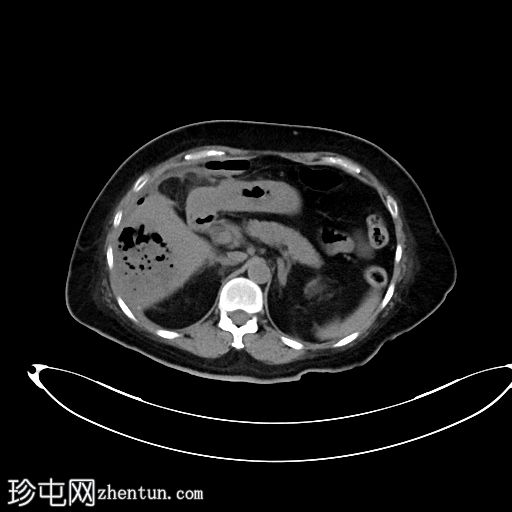

超声检查

2.png

肝胆系统

3.png

肝脏第6和第7段可见多个高回声气体腔,遮挡肝脏后部

肝脏其他部位形态及回声纹理正常

胆总管扩张,无结石,肝内胆管未见扩张

其他方面正常无游离液体